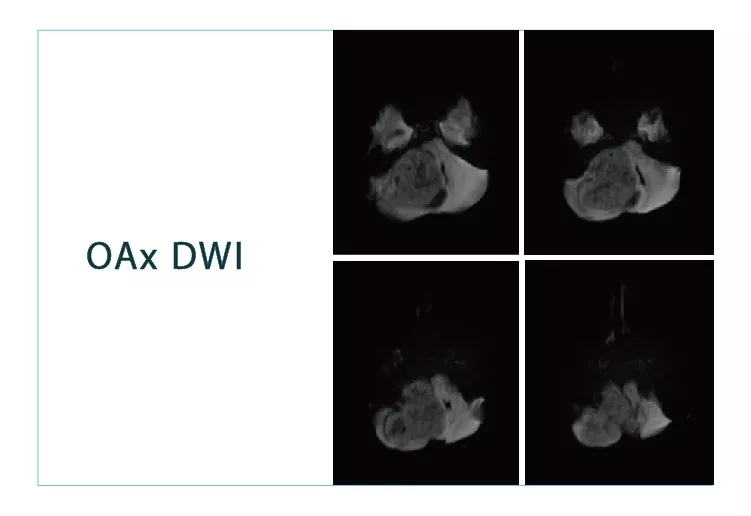

【朗润影像档案】磁共振影像病例分享(编号20180831)